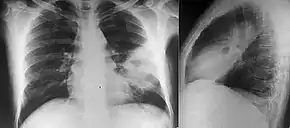

Chest X-ray showing opacity of the left middle and lower areas of the lung.[6]

Diabetes mellitus is one of the most important risk factors in developing melioidosis. The disease should be considered in anyone who has spent time in endemic areas who develops a fever, pneumonia, or abscesses in their liver, spleen, prostate, or parotid gland.[1] The clinical manifestation of the disease can range from simple skin changes such as abscesses or ulcerations to severe organ problems.[8] The commonest organs affected are liver, spleen, lungs, prostate, and kidneys. Among the most common features are bacteremia (in 40 to 60% of cases), pneumonia (50%), and septic shock (20%).[1][9] People with only pneumonia may have a prominent cough with sputum and shortness of breath. However, those with septic shock together with pneumonia may have minimal coughing.[2] Results of a chest X-ray can range from diffuse nodular infiltrates in those with septic shock to progressive consolidation located most commonly in the upper lobes for those with pneumonia only. Pleural effusion and empyema are more common for melioidosis affecting lower lobes of the lungs.[2] In 10% of cases, people develop secondary pneumonia caused by other bacteria after the primary infection.[3] In northern Australia, 60% of the infected children presented with only skin lesions, while 20% presented with pneumonia.[3]

Various imaging modalities can also help with the diagnosis of melioidosis. In acute melioidosis with the spreading of the bacteria through the bloodstream, the chest X-ray shows multifocal nodular lesions. It may also show merging nodules or cavitations. For those with acute melioidosis without the spread to the bloodstream, chest x-ray most commonly shows upper lobe consolidation or cavitations.[10] In chronic melioidosis, the slowly progressing of upper lobe consolidation of the lungs resembles tuberculosis.[10] For abscesses located in other parts of the body apart from the lungs, especially in the liver and spleen, CT scan has higher sensitivity when compared with an ultrasound scan. In liver and splenic abscesses, an ultrasound scan shows "target-like" lesions while CT scan shows "honeycomb sign" (abscess with loculations separated by thin septa) in liver abscesses.[10] For melioidosis involving the brain, MRI have higher sensitivity than a CT scan in diagnosing the lesion. MRI shows ring-enhancing lesions for brain melioidosis.[10]